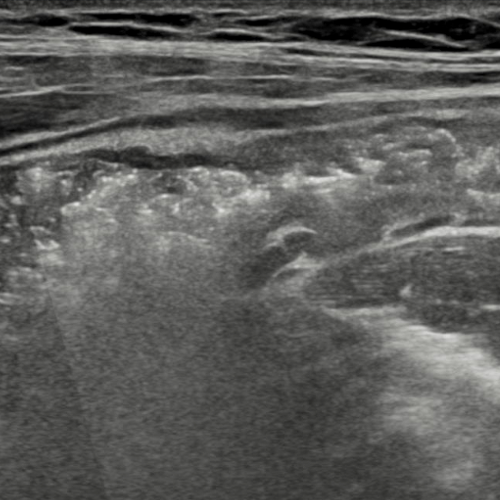

MRI and intestinal ultrasound are increasingly used for whole-bowel assessment, but cine loops and dynamic scans can be time-consuming to review and difficult to standardise.

Motilent is exploring integration of MRI, intestinal ultrasound, capsule endoscopy, and histopathology, as well as patient-reported outcomes via IBDmate, to create a more comprehensive understanding of IBD activity.